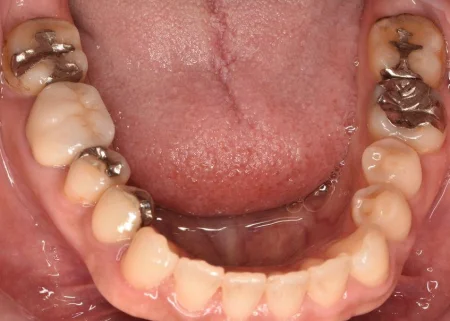

治療前

| カウンセリング・診断結果 | 診察したところ、奥歯には銀でできた詰め物や被せ物がいくつも入っており、お口を開けると目立つ状態でした。 |